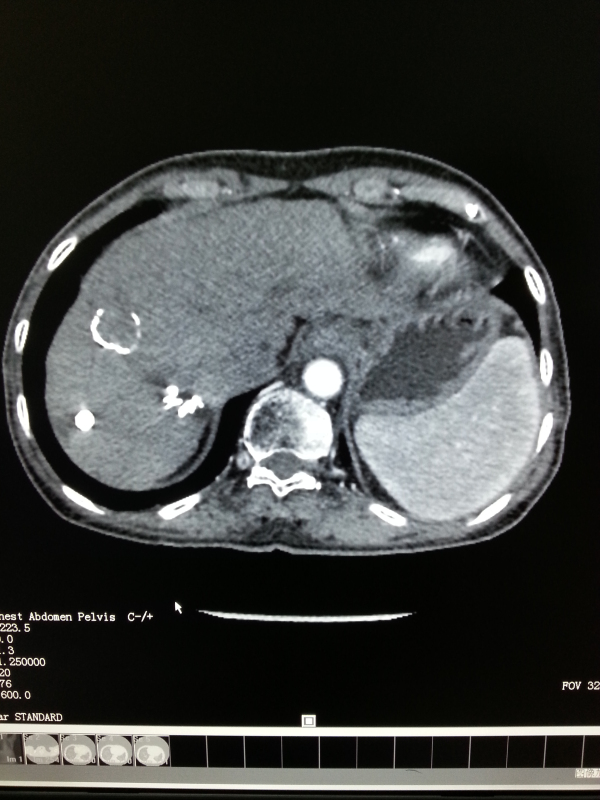

贵港黄女士是2013年确诊为胆管细胞癌,当时癌肿已有6-7厘米大。经过十天左右的射波刀治疗,同时运用中草药扶正抑制癌肿治疗。持续服用中药9个月后,她再次来到了瑞康医院进行磁共振检查,让黄女士感到惊喜的是:肝脏巨大肿块竟然明显缩小了,而且其他部位没见新病灶。如此良好的效果是中西医结合“三联疗法”的作用。

黄女士治疗7个月后肝肿瘤消失